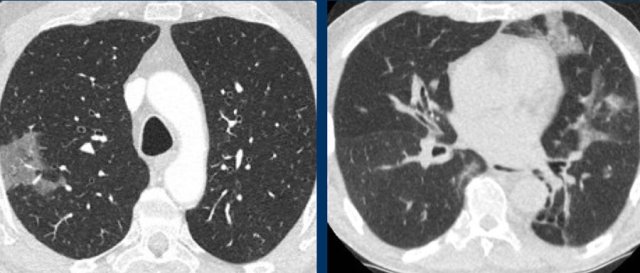

Drug-induced pneumonitis

Drugs can cause CT patterns similar to confirmatory patterns of COVID-19, including ground glass, peripheral consolidations, crazy paving and organizing pneumonia patterns.

The appropriate clinical setting of potentially pneumotoxic drugs and clear improvement after drug withdrawal (right) helps in suggesting this differential diagnosis.

A list of pneumotoxic drugs and the findings on CT is found on www.pneumotox.com.

Radiation pneumonitis

Inflammatory and fibrotic changes associated with radiotherapy can cause peripheral ground-glass and consolidations in the area of the radiation therapy field.

However, bilateral organizing pneumonia outside the radiation field can also occur, mimicking one of the confirmatory feature of COVID-19.

Correlation with the radiotherapy field and stationary location of abnormalities over time can virtually always confirm radiation pneumonitis.